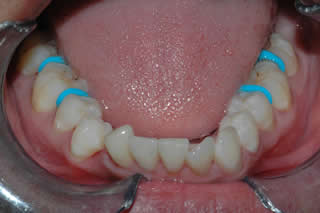

Orthodontic / Implant:

Lower left canine was extracted, thus teeth start drfting and tilting.

Space is re-created with orthodontics first, single implant was placed to replace the extracted canine.